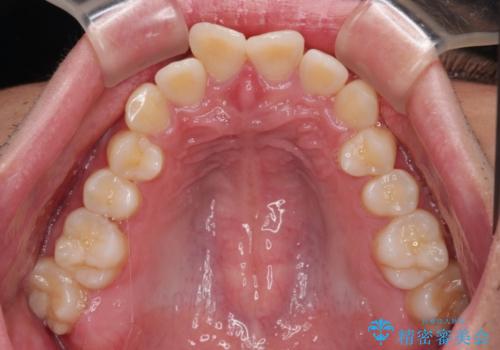

- ディープバイトと上顎前歯の突出、奥歯の咬み合わせを気にして来院された患者様です。

上顎歯列は全体的に前方位にあり、それが原因で深い咬み合わせとなり、突き上げにより上顎前歯が前方に飛び出している状態でした。

また、左右ともに上顎最後臼歯が頬側に転位している鋏状咬合となっていました。

インビザラインによる矯正治療をご希望でしたが、上顎歯列の前方位と鋏状咬合を確実に改善することを目的として、補助装置を併用することとしました。